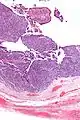

| Micrograph of transitional cell carcinoma of the ovary. H&E stain. |

Transitional cell carcinoma of the ovary (TCC of the ovary) is a rare type of ovarian cancer that has an appearance similar to urothelial carcinoma (also known as transitional cell carcinoma).[1]

TCC of the ovary is diagnosed by examination of the tissue by a pathologist. It has a characteristic appearance under the microscope and distinctive pattern of immunostaining.[2]

Very high mag.